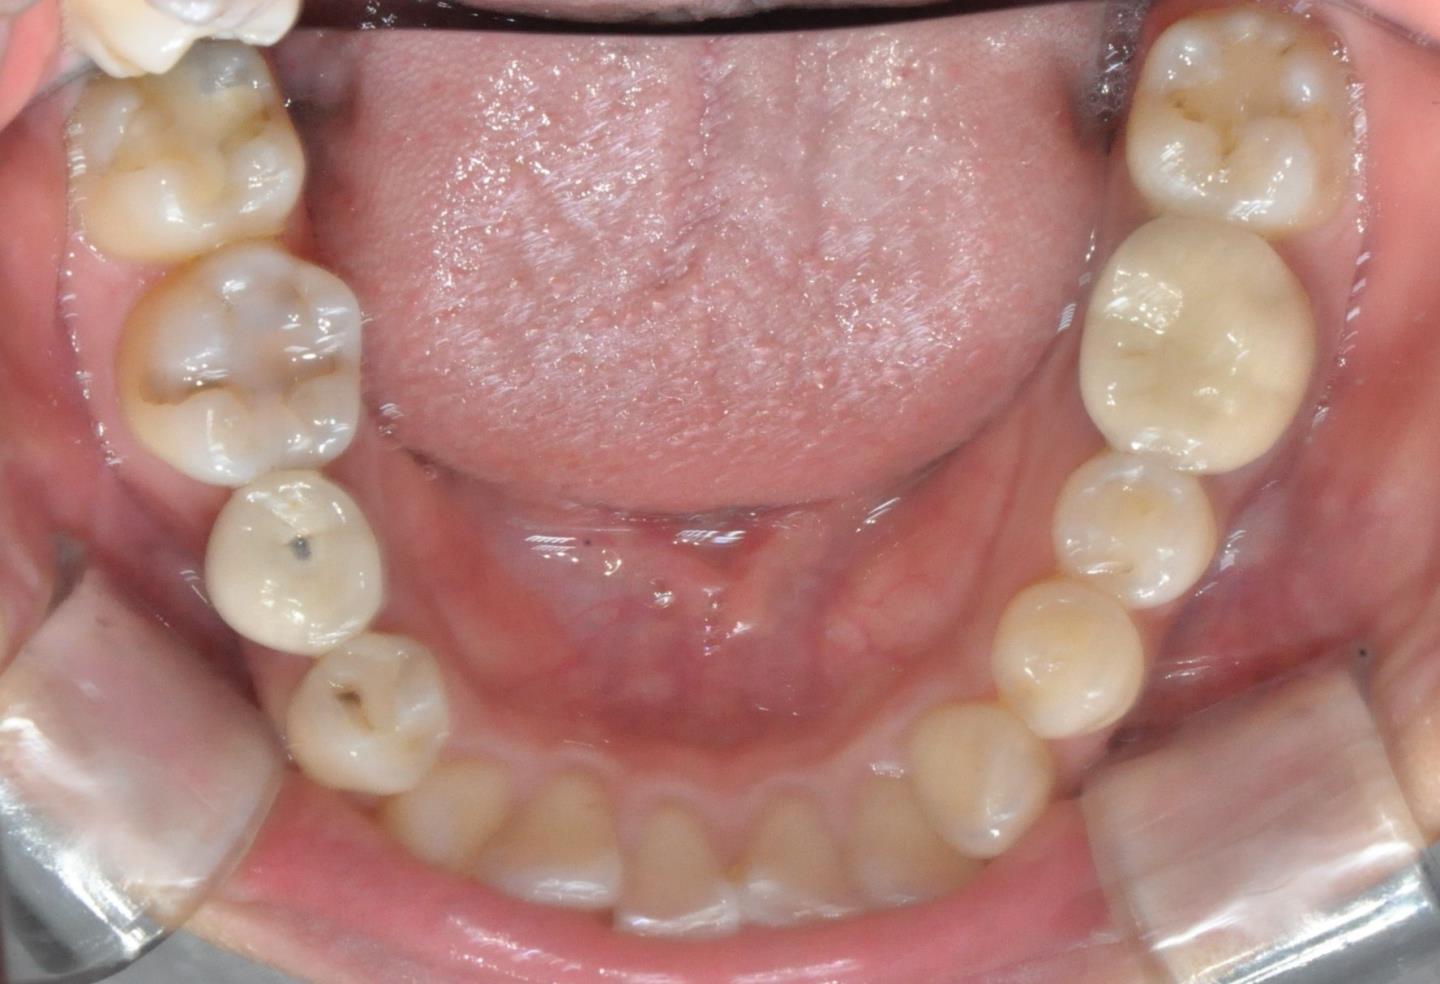

그때 가서 찍은 사진이고,

치료 받기 전 찍은 사진입니다.